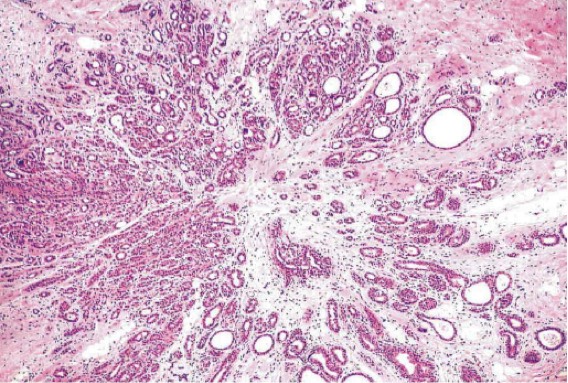

1085. При маммографическом исследовании в молочной железе обнаружен фокус фиброза звездчатой формы. при гистологическом исследовании на малом увеличении изменение по форме напоминает цветок. участок фиброза в центре содержит сдавленные протоки и дольки, окруженные железами с различной степенью дилатации, гиперплазии, аденозом. вероятным диагнозом является